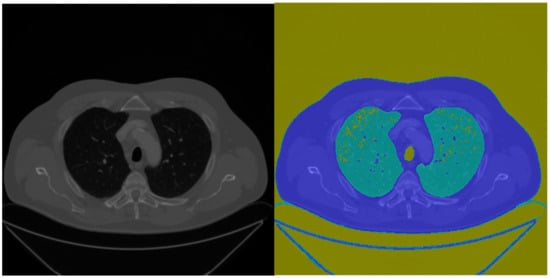

This study used k-means clustering to obtain the air (yellow in Figure 3) and quasi-air (light blue) pixels in the CT. The edge mask was removed by representation to complete the lung circling, and the internal voids were removed by morphology, as shown in Figure 4.

Figure 3.

K-means initially segmented image.